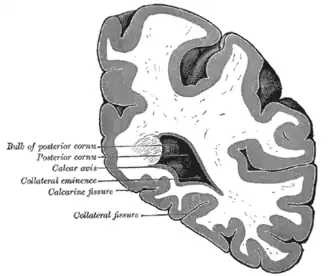

Coronal section through posterior cornua of lateral ventricle. (Collateral fissure labeled at bottom center.)

Coronal section through posterior cornua of lateral ventricle. (Collateral fissure labeled at bottom center.) -